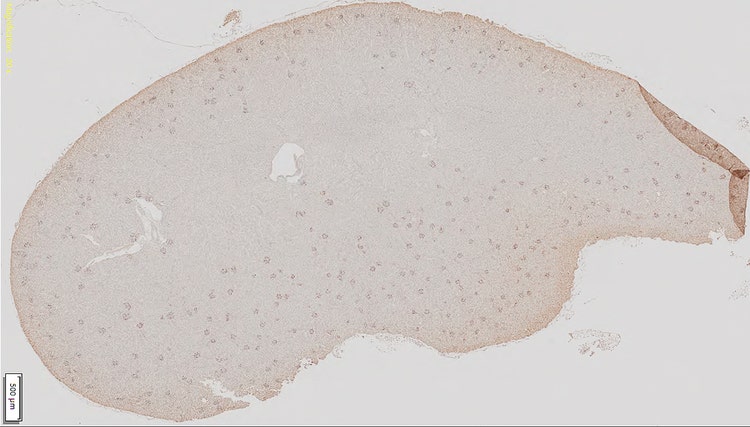

1. Une nouvelle lame est numérisée avec le scanner numérique de lames SLIDEVIEW™ VS200 pour produire une image.

nouvelle image numérique

scanner numérique de lames SLIDEVIEW™ VS200